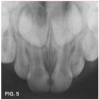

Case 2. This 2-year-old boy had mesial caries lesions of his maxillary central incisors associated with chronic plaque accumulation and lack of tooth brushing or flossing by the parents (Figure 5 and Figure 6). The parents, who were given extensive instructions to remedy the oral hygiene problem, consented to SDF application despite the black discoloration. They related that they not only wanted to avoid a repair appointment for the child, but they also liked the idea that traditional restoration could be delayed until he was older and could more easily tolerate treatment. Three months after initial SDF application, the solution was reapplied (Figure 7).

Fig 5. Mesial caries lesions in 2-year-old patient.

Fig 5

Fig 6. Much plaque accumulation; no oral home care apparent.

Fig 6

Fig 7. 3 months after SDF application, before renewed application.

Fig 7